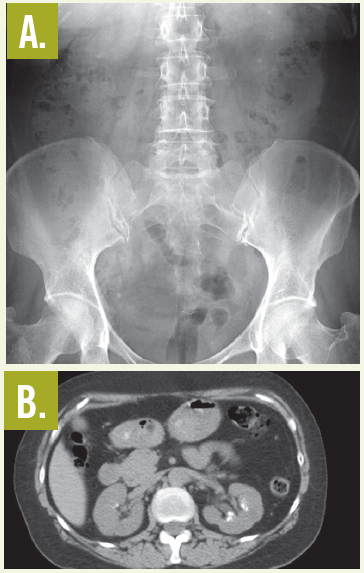

Laboratory testing. An abdominal radiograph (A) and a CT scan of the kidneys, ureters, and bladder (B) showed bilateral renal calcifications. On the right, the largest was 3 mm, and on the left, multiple punctate calcifications were evident. Urinalysis was positive for trace blood and trace leukocytes. The analysis of the stone revealed triamterene composition. The patient underwent successful placement of ureteral stents to help passage of the stones followed by lithotripsy.

Treatment. The treatment consists of discontinuation of medication and lithotripsy, because the calculi cannot be dissolved by pH manipulation.3 On plain radiographs, triamterene stones are—as in this case—faintly radiopaque and are less dense than calcium oxalate stones. They are more detectable on a CT scan of the kidneys, ureters, and bladder.